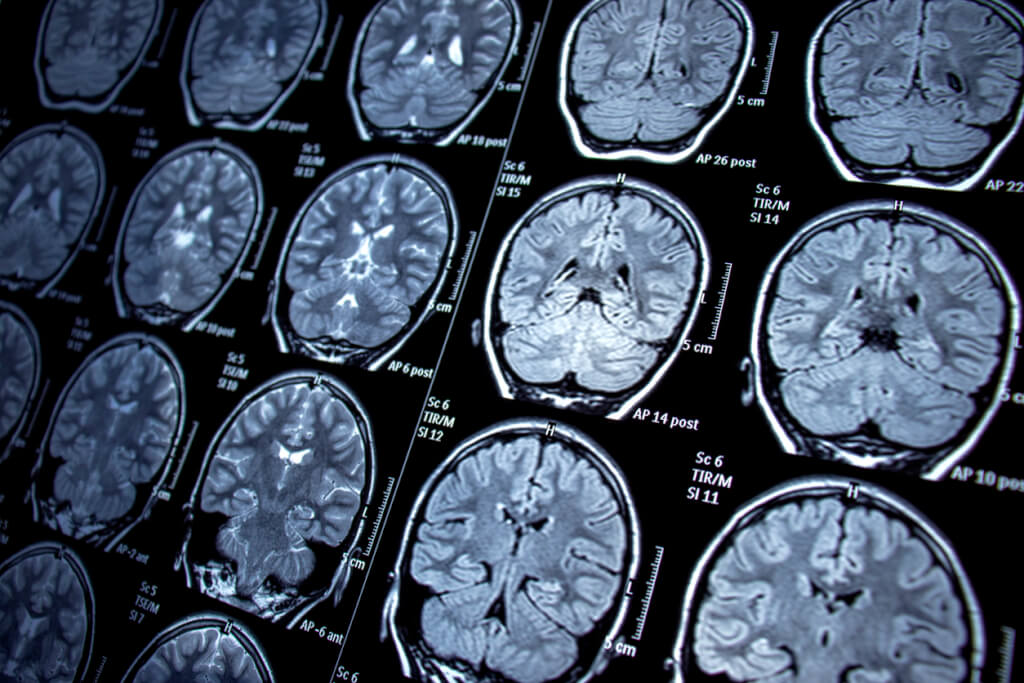

Фото: IStock

Опухоли глиобластомы быстро растут, проникают в ткани головного мозга и развивают устойчивость к химио- и лучевой терапии, что затрудняет борьбу с ними. Кроме того, любые раковые клетки, которые остались после лечения, как правило, возвращаются с удвоенной силой, хотя предпринимаются усилия, чтобы этого не произошло.